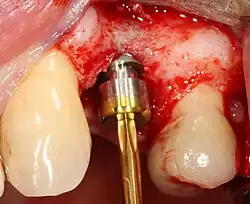

Most implant systems have five basic steps for placement of each implant:[28]: 214–221

- Placement of the implant: The implant screw is placed and can be self-tapping;[50]: 100–102 otherwise, the prepared site is tapped with an implant analog. It is then screwed into place with a torque controlled wrench[54] at a precise torque so as not to overload the surrounding bone (overloaded bone can die, a condition called osteonecrosis, which may lead to failure of the implant to fully integrate or bond with the jawbone).

- Tissue adaptation: The gingiva is adapted around the entire implant to provide a thick band of healthy tissue around the healing abutment. In contrast, an implant can be "buried", where the top of the implant is sealed with a cover screw and the tissue is closed to completely cover it. A second procedure would then be required to uncover the implant at a later date.